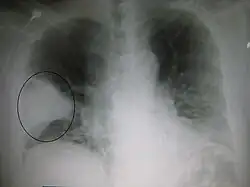

Right upper lobe pneumonia as marked by the circle. -

Left upper lobe pneumonia with a small pleural effusion.